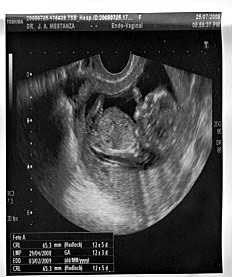

“Busco una familia cariñosa para mi bebé”, publicó Luz Choque Quino en Internet desde Cochabamba, su ciudad. La joven que ahora tiene 22 años había vivido un tiempo, allá por 2007, en Buenos Aires, donde trabajó en un taller de costura. Volvió a Bolivia presionada por uno de sus hermanos, que no aprobaba su noviazgo con Alfredo. Un tiempo después, ella se escapó para reencontrarse con su enamorado. Pero la presión familiar la hizo regresar de nuevo a su país, sin siquiera despedirse del hombre del que en esos tres meses había quedado embarazada. En realidad, ella todavía no lo sabía. Cuando se enteró, lo llamó por teléfono para avisarle, pero sólo escuchó reproches y descrédito. Desesperada porque el padre de su hijo no quería hacerse cargo, Luz puso el aviso en Internet para ofrecer al niño. Se contactó con una supuesta familia y viajó a Rosario embarazada de siete meses, el año pasado, para entregar a su hijo. No se encontró exactamente con la familia que iba a “adoptarlo”, sino con una abogada, Sandra de Miguel, intermediaria en la transacción. Luz asegura que no vendió a su bebé. Apenas le dieron algo de dinero para que vuelva a su país, luego del nacimiento. La profesional le pidió su documento –mientras ella transitaba el final del embarazo– y cambió su domicilio por uno falso.

Luz vivió dos meses en un hostel y en la madrugada del 30 de mayo, cuando los dolores de parto eran fuertes, fue al hospital Centenario. A las 10 de la mañana nació su bebé, Lucio. “Cuando lo vi tan chiquitito, me dije que era mío y no se lo iba a dar a nadie. Que era mi otro yo”, cuenta. Con cierta ingenuidad, fue a decirle a la abogada que se había arrepentido, pero recibió insultos y frases despectivas. De Miguel le aseguró que tendría otra instancia, en las audiencias de conciliación, para quedarse con su hijo, pero que iba a cambiar de idea. Bajo presión, Luz cedió al niño, con la esperanza de recuperarlo en la primera audiencia. No sabía que las citaciones del Tribunal Colegiado de Familia llegarían a un domicilio falso, y ella jamás podría enterarse. Le llevó ocho meses de transitar por Tribunales y batallar hasta llegar al Consulado de Bolivia. Pero recuperó a su hijo. Ahora, está feliz, aunque sigue muy conmovida.